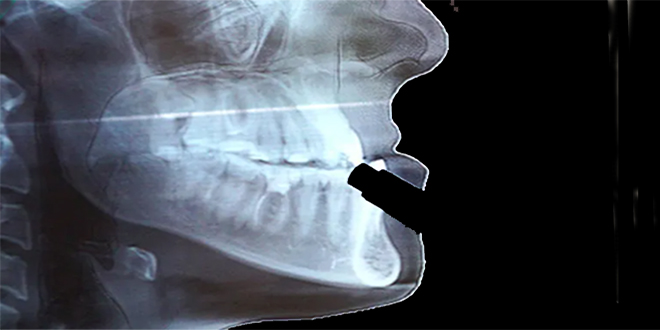

أزاح فريق بحثي من جامعة كيوتو اليابانية الستار عن إنجاز علمي مهم يتضمن تطوير عضيات (نُظم عضوية مصغرة) تُحاكي تكوُّن عظم الفك البشري، وذلك بالاستعانة بالخلايا الجذعية، ما يفتح المجال أمام إمكانية تطبيق هذه العضيات في علاجات تجديد عظم الفك عبر الزرع، واستخدامها كنماذج مرضية لتطوير علاجات لأمراض مثل خلل التنسج العظمي، وفقاً لصحيفة أساهي اليابانية.

وبحسب الدراسة التي نشرت نتائجها أمس في المجلة الدولية للعلوم “Nature Biomedical Engineering”، تمكن الباحثون بقيادة الأستاذين المساعدين سوتا موتويكي وإيكيا ماكوتو من قسم البحوث السريرية التطبيقية بجامعة كيوتو، من تصنيع هذه العضيات، حيث اعتمدوا في ذلك على عدة خطوات تبدأ من الخلايا العرفية العصبية البشرية المشتقة من الخلايا الجذعية، وصولاً إلى الخلايا الأديمية الظاهرة المتوسطة، لإنتاج بنية ثلاثية الأبعاد مطابقة لعظم الفك.